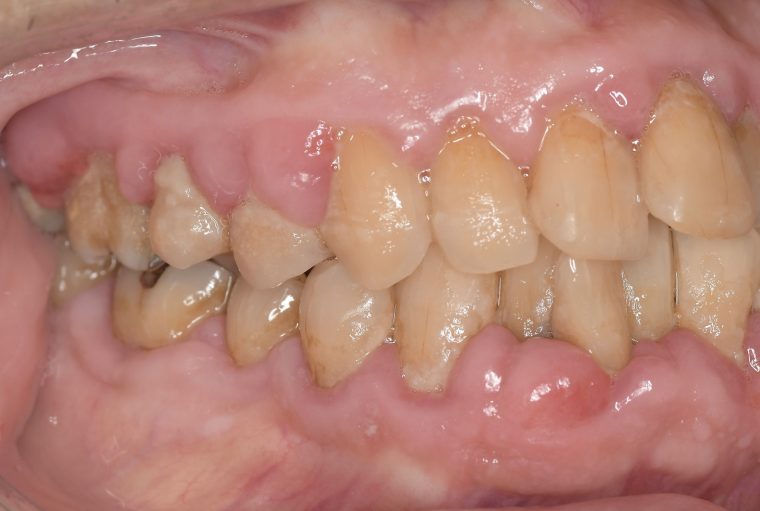

CASE 7

Before

After

基本情報

| 年齢・性別 | 48歳・男性 |

| 主訴 | 定期検診 |

| 治療内容 | スケーリング |

| 治療期間 | 60分 |

| 治療費 | 1,500円(保険診療) |

| リスク・副作用 | 知覚過敏、出血 |

| 治療方針 | まず歯肉縁上歯石を除去して、スッキリとした感覚や滑らかな舌ざわりを実感してもらいました。この状態を保てるように歯磨きの仕方や、歯周病についてお話ししました。 今後は歯肉縁下歯石を除去して、歯周病治療を行っていきます。 |

| 担当者所見 | 久しぶりの歯科医院への受診でした。 治療に慣れていないため、少しずつ歯石を除去していきました。 |